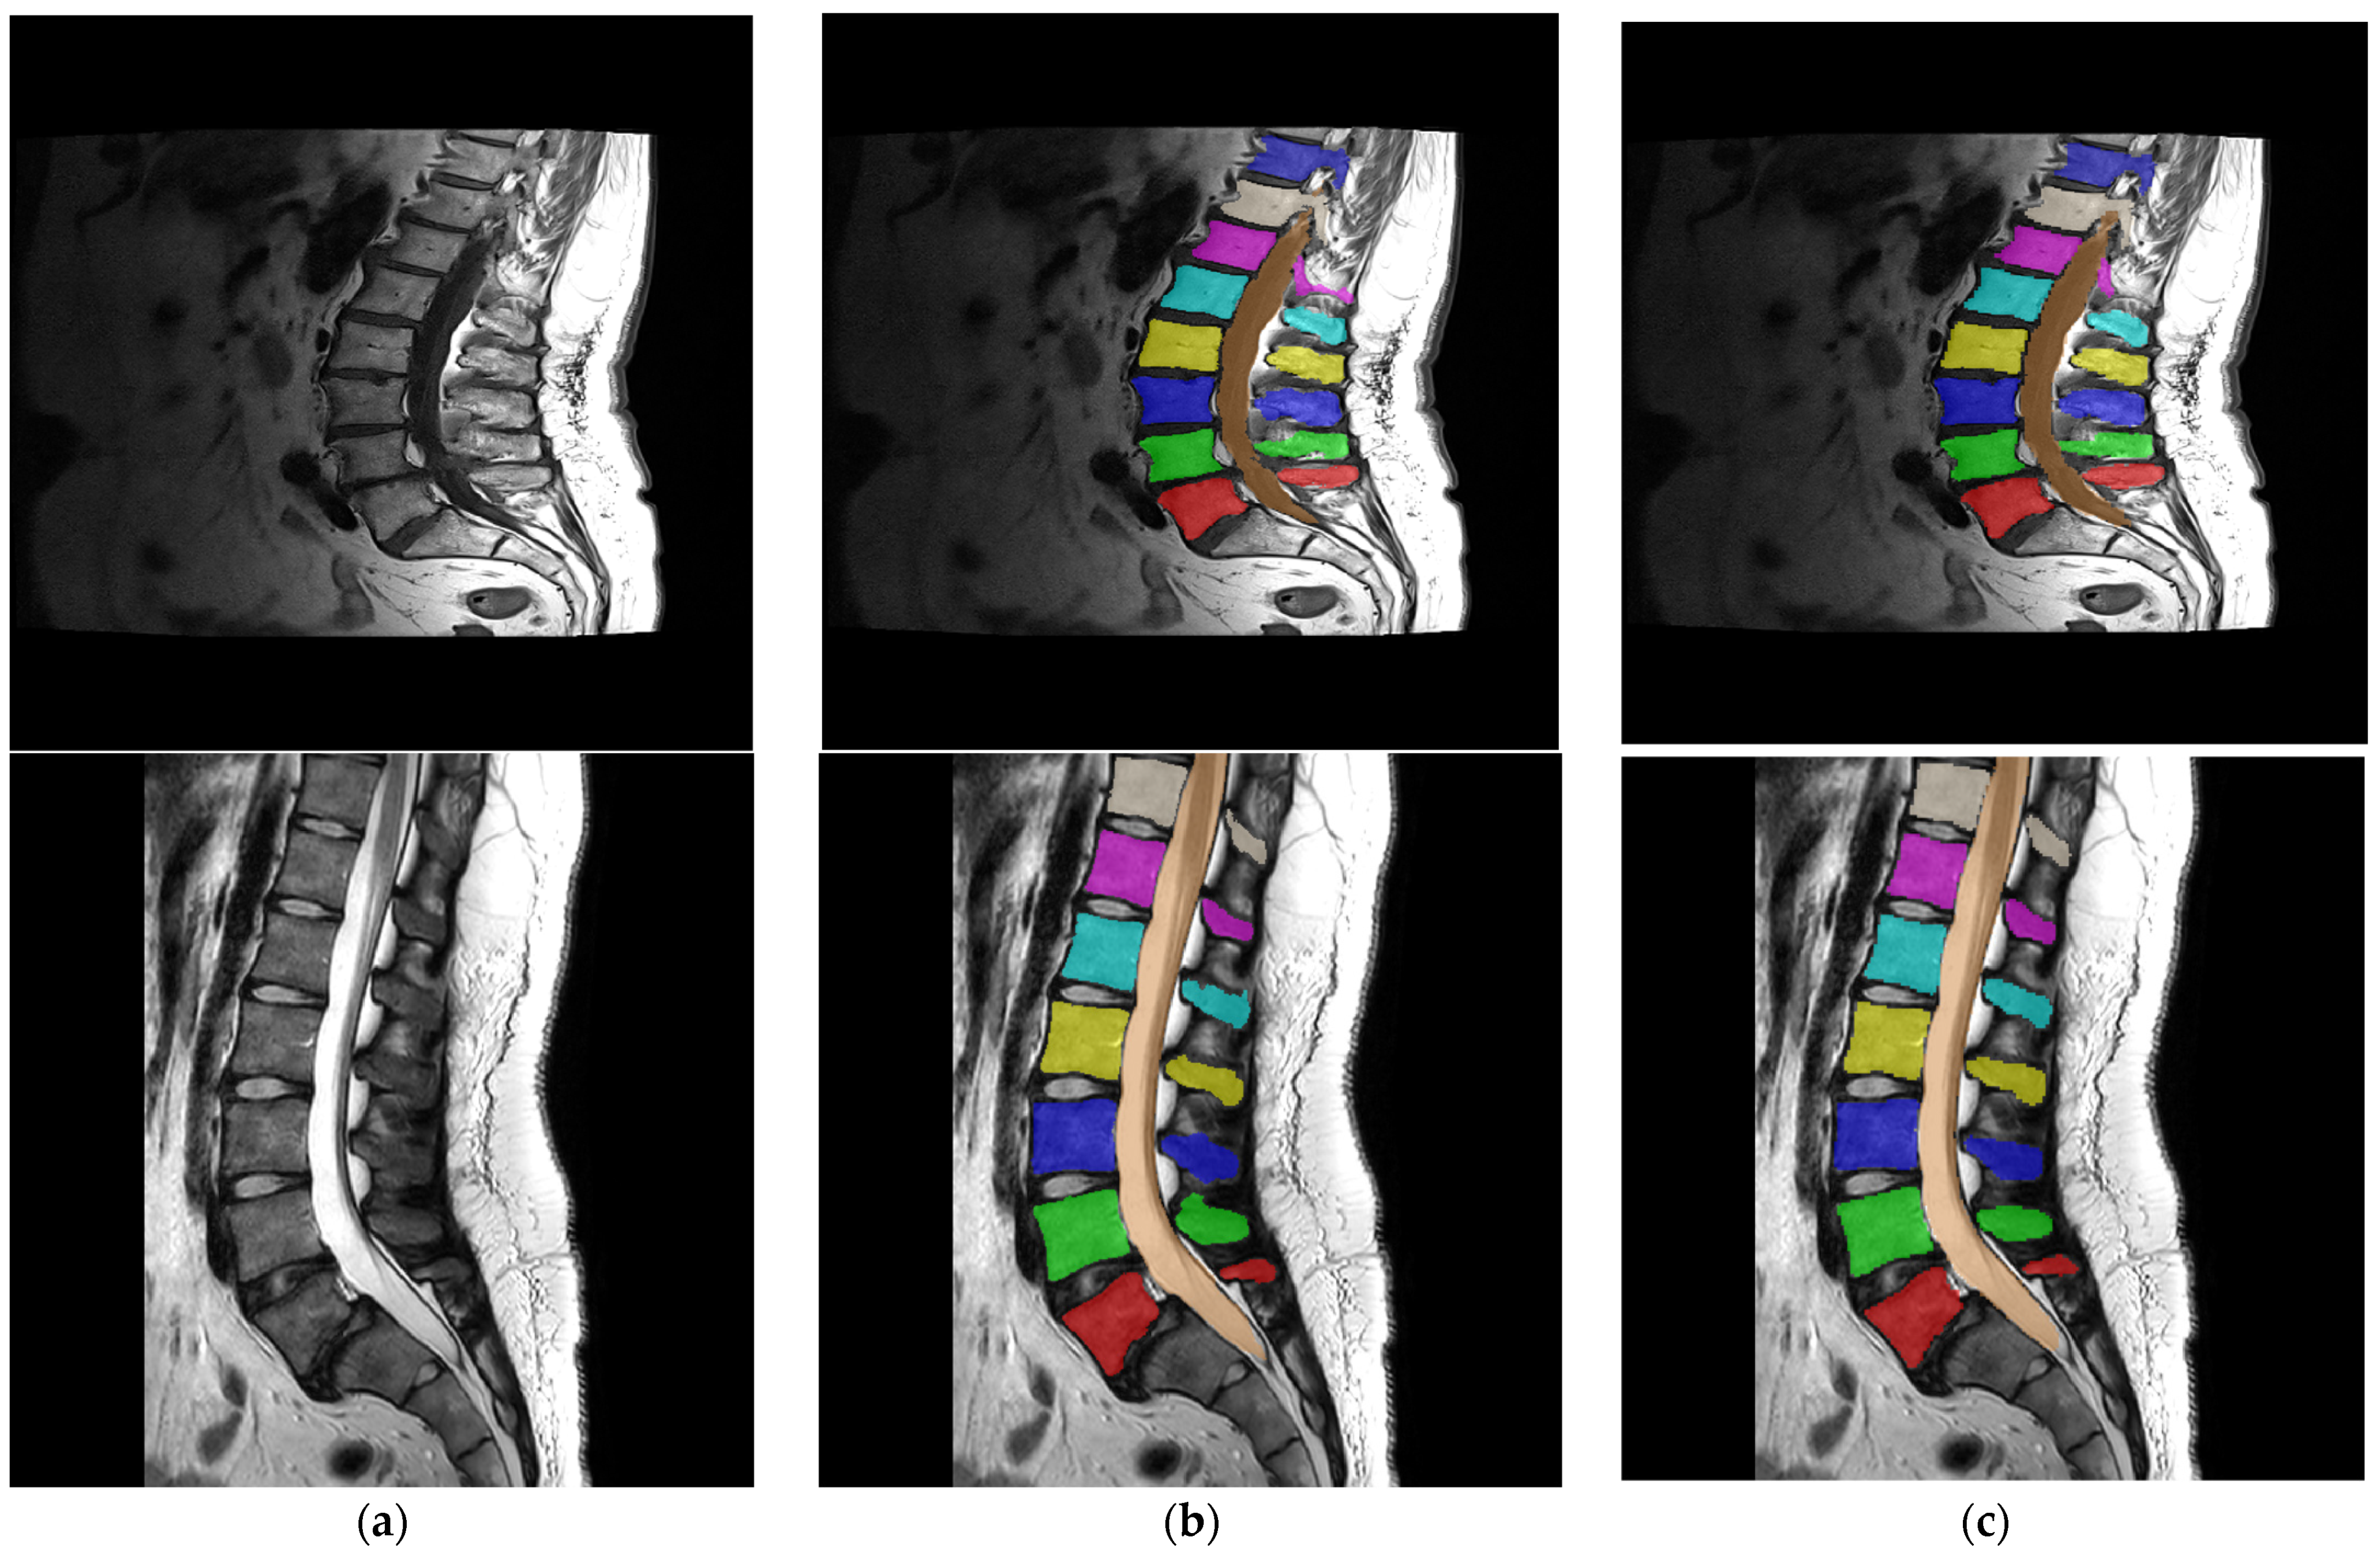

The performance of the BRAU-Net++ network can be directly compared with that of the nnU-Net neural network, as both networks were trained with the same dataset. The results of the DSC evaluation metric for nnU-Net are 0.92 ± 0.05 for the vertebrae and 0.92 for the spinal canal. The average DSC value for BRAU-Net++ for the vertebrae is 0.914 ± 0.007, which is in the range of the values reported by nnU-Net. The DSC value for the spinal canal is 0.902 and thus below the result of the nnU-Net DSC score. Figure 4 shows examples of original images, ground truth segmentation and predictions for individual images from T1- and T2-weighted series.

Figure 4. (a) Single mid-sagittal T1-weighted (upper) and T2-weighted (lower) image from a randomly chosen series. (b) Ground truth segmentations overlayed on the corresponding image from (a). (c) Prediction segmentation images of the trained neural network model. Different colors represent each of the 9 segmentation classes, which are labeled 1–9 in the segmentation masks.